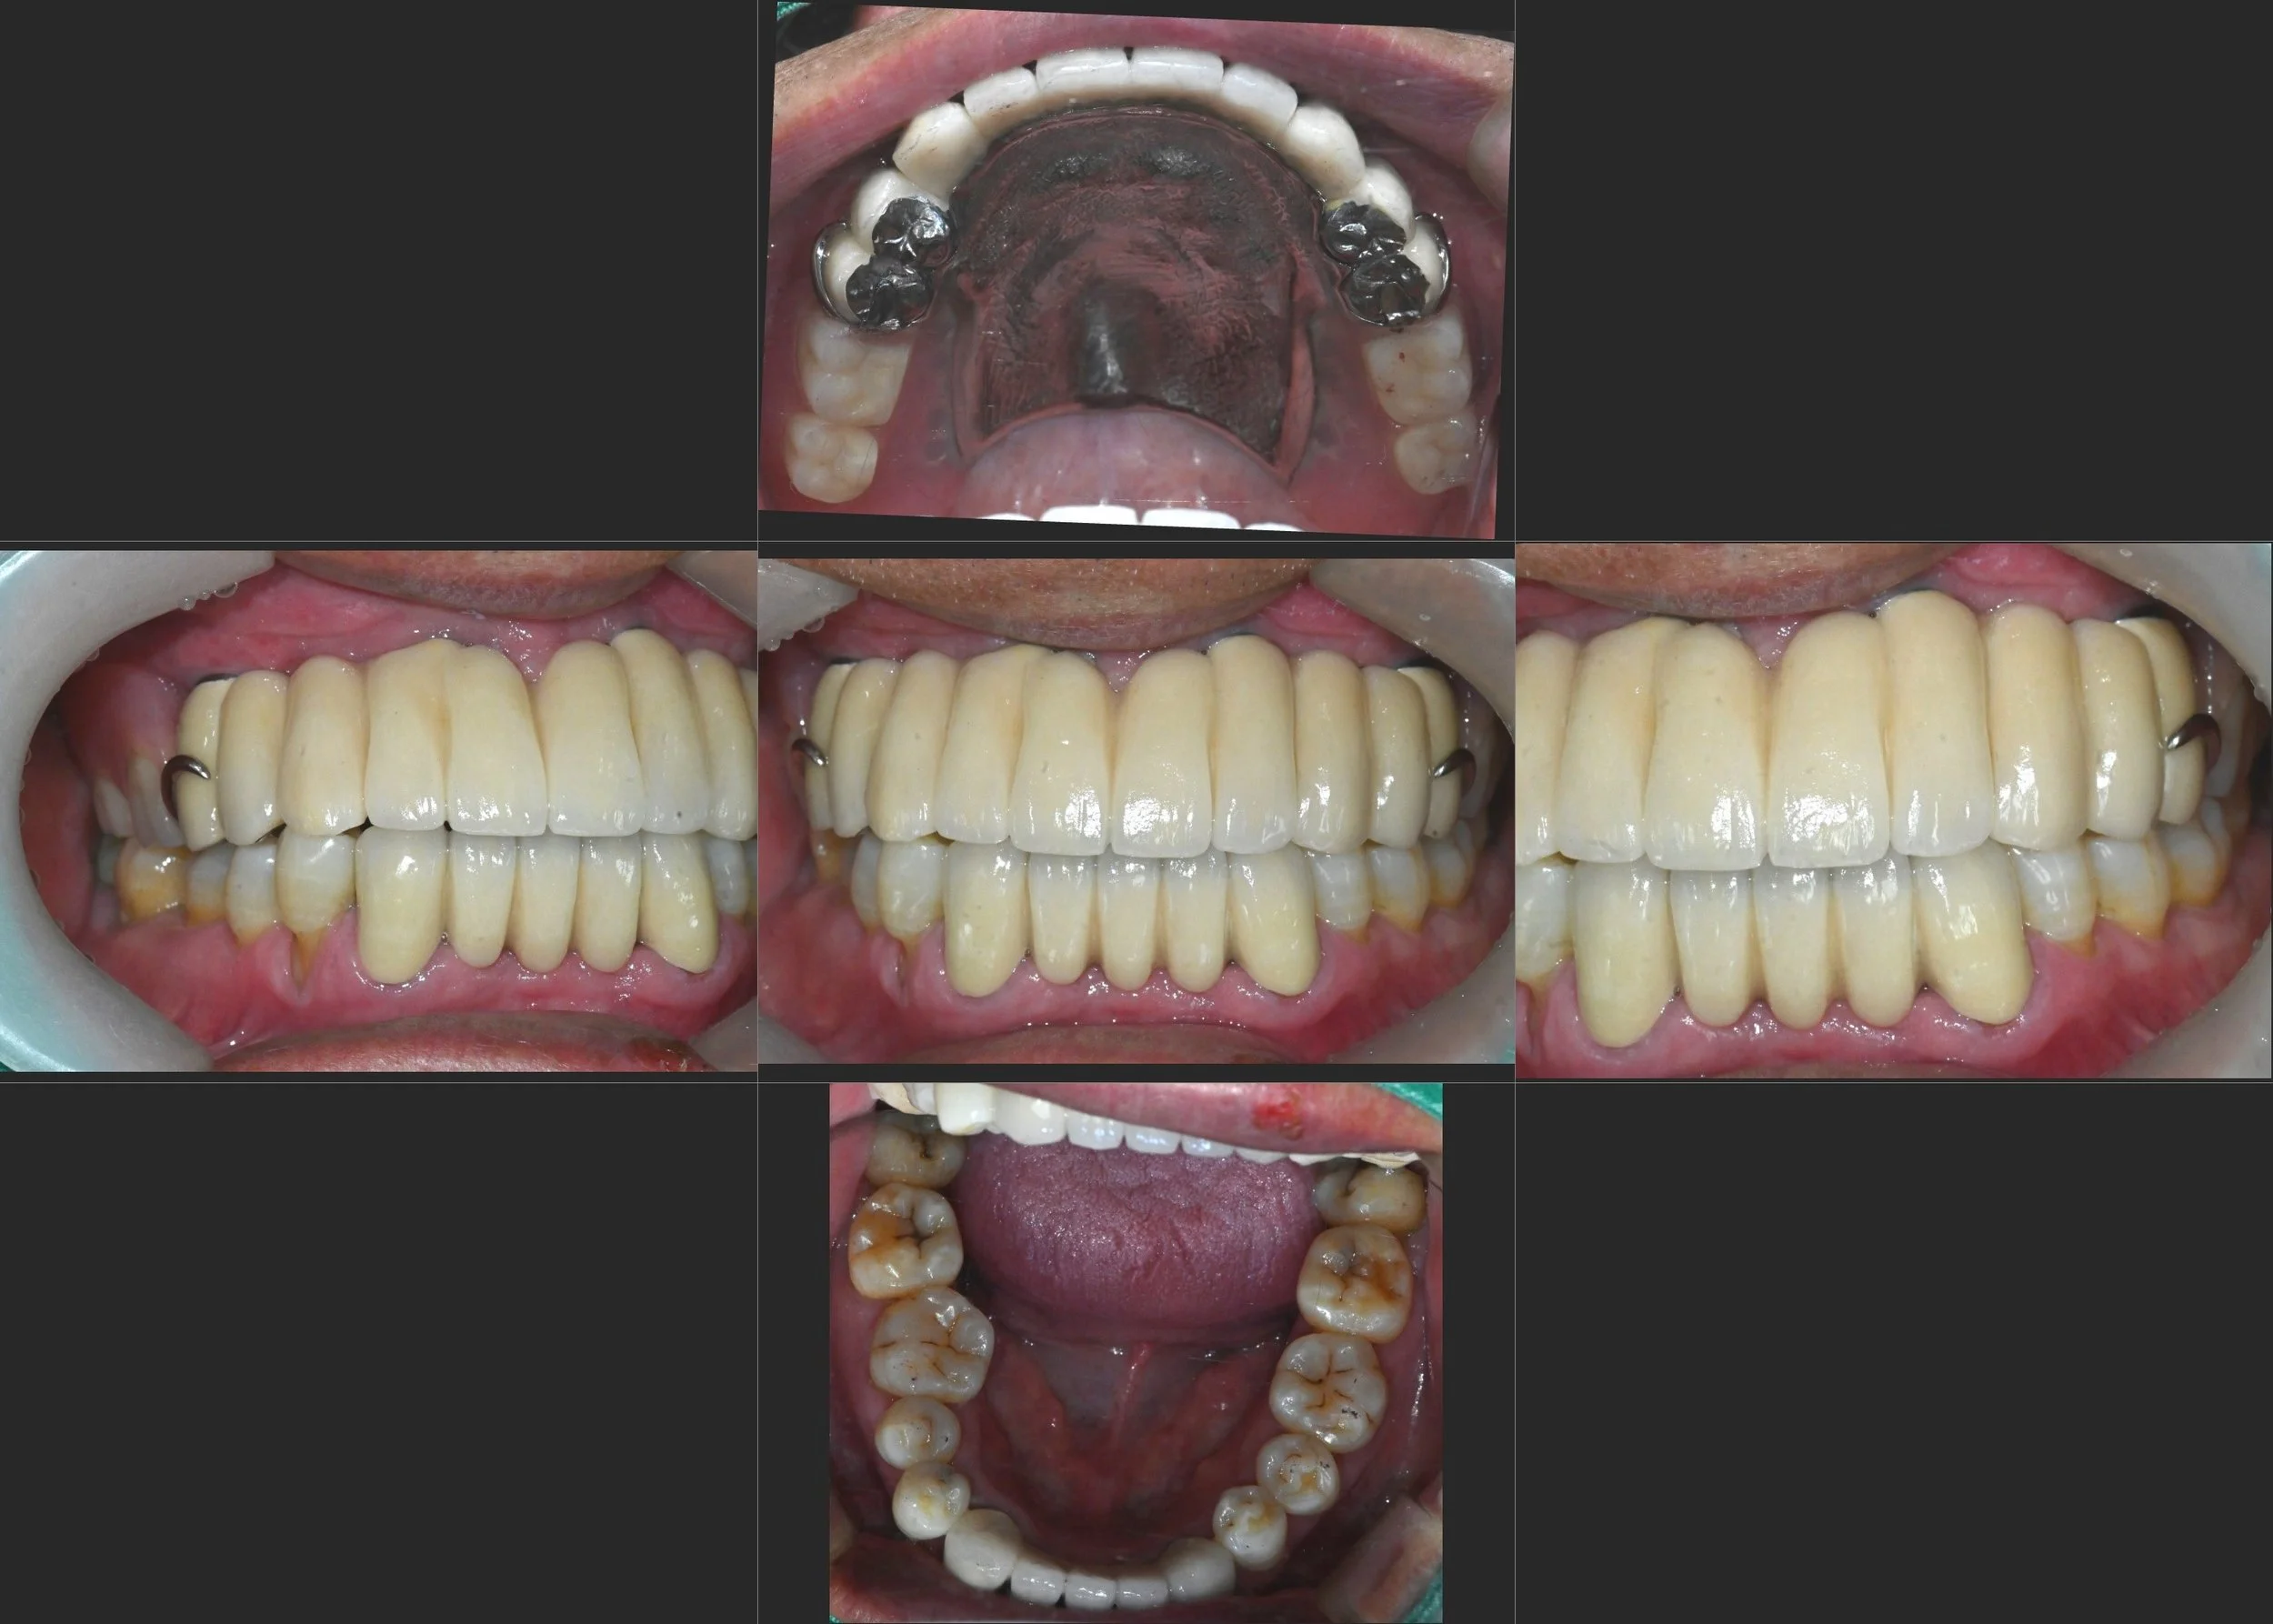

INTRA ORAL - AFTER

A hybrid treatment strategy was planned to balance function, aesthetics, and cost.

• Anterior implants were placed to support aesthetic and functional demands

• Posterior support was achieved using an implant-supported removable partial denture (ISRPD)

• A five-unit anterior bridge was designed using three pontics, taking into account the limited mandibular anterior space

• Occlusal design focused on distributing forces evenly and reducing overload on remaining abutment teeth

This approach allowed restoration of function and appearance while avoiding the biological and financial burden of full-arch rehabilitation.